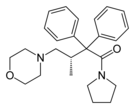

Beta-Amino Ketones

Diphenylmethylpiperazines